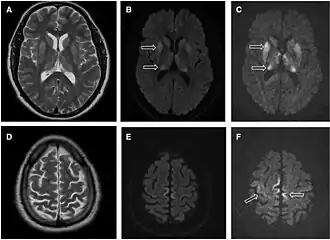

• MRI with diffusion weighted inversion (DWI) and fluid-attenuated inversion recovery (FLAIR) shows a high signal intensity in certain parts of the cortex (a cortical ribboning appearance), the basal ganglia, and the thalami.[42] The most common presenting patterns are simultaneous involvement of the cortex and striatum (60% of cases), cortical involvement without the striatum (30%), thalamus (21%), cerebellum (8%) and striatum without cortical involvement (7%). In populations with a rapidly progressive dementia (early in the disease process), MRI has a sensitivity of 91% and specificity of 97% for diagnosing CJD.[46] The MRI changes characteristic of CJD may also be seen in the immediate aftermath (hours after the event) of autoimmune encephalitis or focal seizures.[42]

Imaging of the brain may be performed during medical evaluation, both to rule out other causes and to obtain supportive evidence for diagnosis. Imaging findings are variable in their appearance and also variable in sensitivity and specificity.[49] While imaging plays a lesser role in diagnosis of CJD,[50] characteristic findings on brain MRI in some cases may precede onset of clinical manifestations.[51]

Brain MRI is the most useful imaging modality for changes related to CJD. Of the MRI sequences, diffuse-weighted imaging sequences are most sensitive.[52] Characteristic findings are as follows:

• Focal or diffuse diffusion-restriction involving the cerebral cortex or basal ganglia. The most characteristic and striking cortical abnormality has been called "cortical ribboning" or "cortical ribbon sign" due to hyperintensities resembling ribbons appearing in the cortex on MRI.[53] The involvement of the thalamus can be found in sCJD, is even stronger and constant in vCJD.[54]

• Varying degree of symmetric T2 hyperintense signal changes in the basal ganglia (i.e., caudate and putamen), and to a lesser extent globus pallidus and occipital cortex.[50]